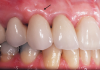

A patient presented with two defective 3-unit fixed partial dentures spanning teeth Nos. 6 through 8 and teeth Nos. 9 through 11 (Figure 7). The defective fixed partial dentures were removed (Figure 8), an impression was made, and traditional provisional fixed partial dentures without ovate pontics were placed. After the impression was sent to the laboratory, the lab technician prepared ovate pontic sites on the stone cast (Figure 9) and fabricated the new definitive bridges. On the day of insertion, the provisional fixed partial dentures were removed (Figure 10), ovate pontic sites were prepared using a teardrop-shaped diamond bur (Figure 11), and the sites were sounded to confirm that there was at least 2 mm from the base of the pontic site to the alveolar bone (Figure 12). The fixed partial dentures were cemented, and the postoperative healing was uneventful (Figure 13).